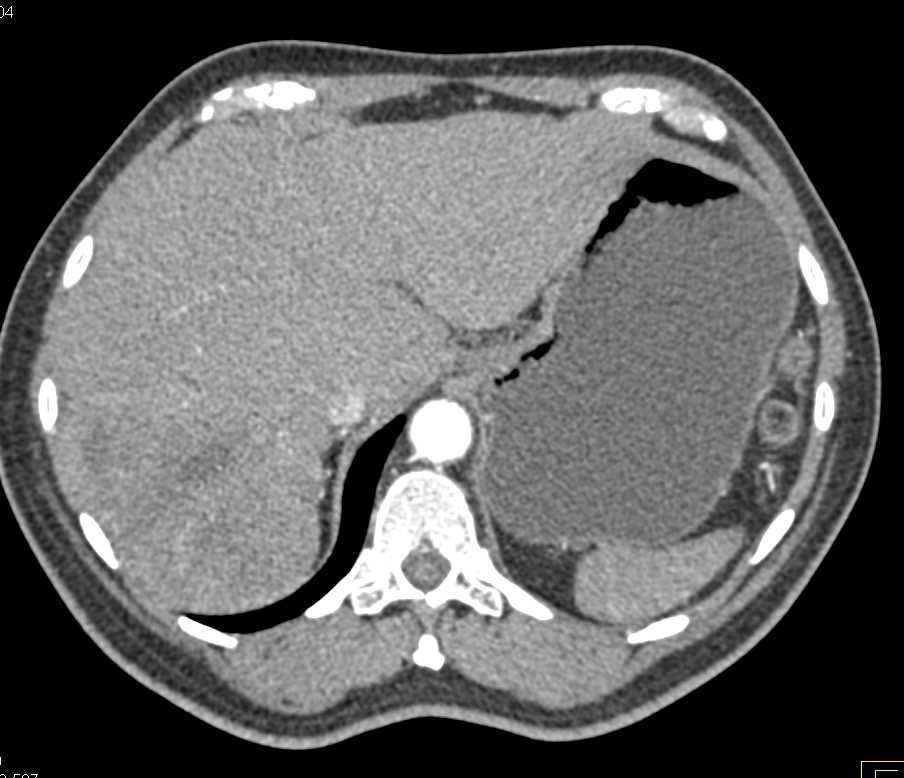

Neuroendocrine Tumor Pancreas